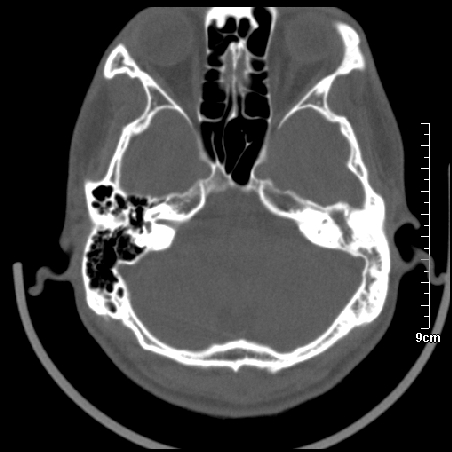

病例2

m/27

左侧板障型乳突。

左侧慢性中耳炎伴胆脂瘤形成。